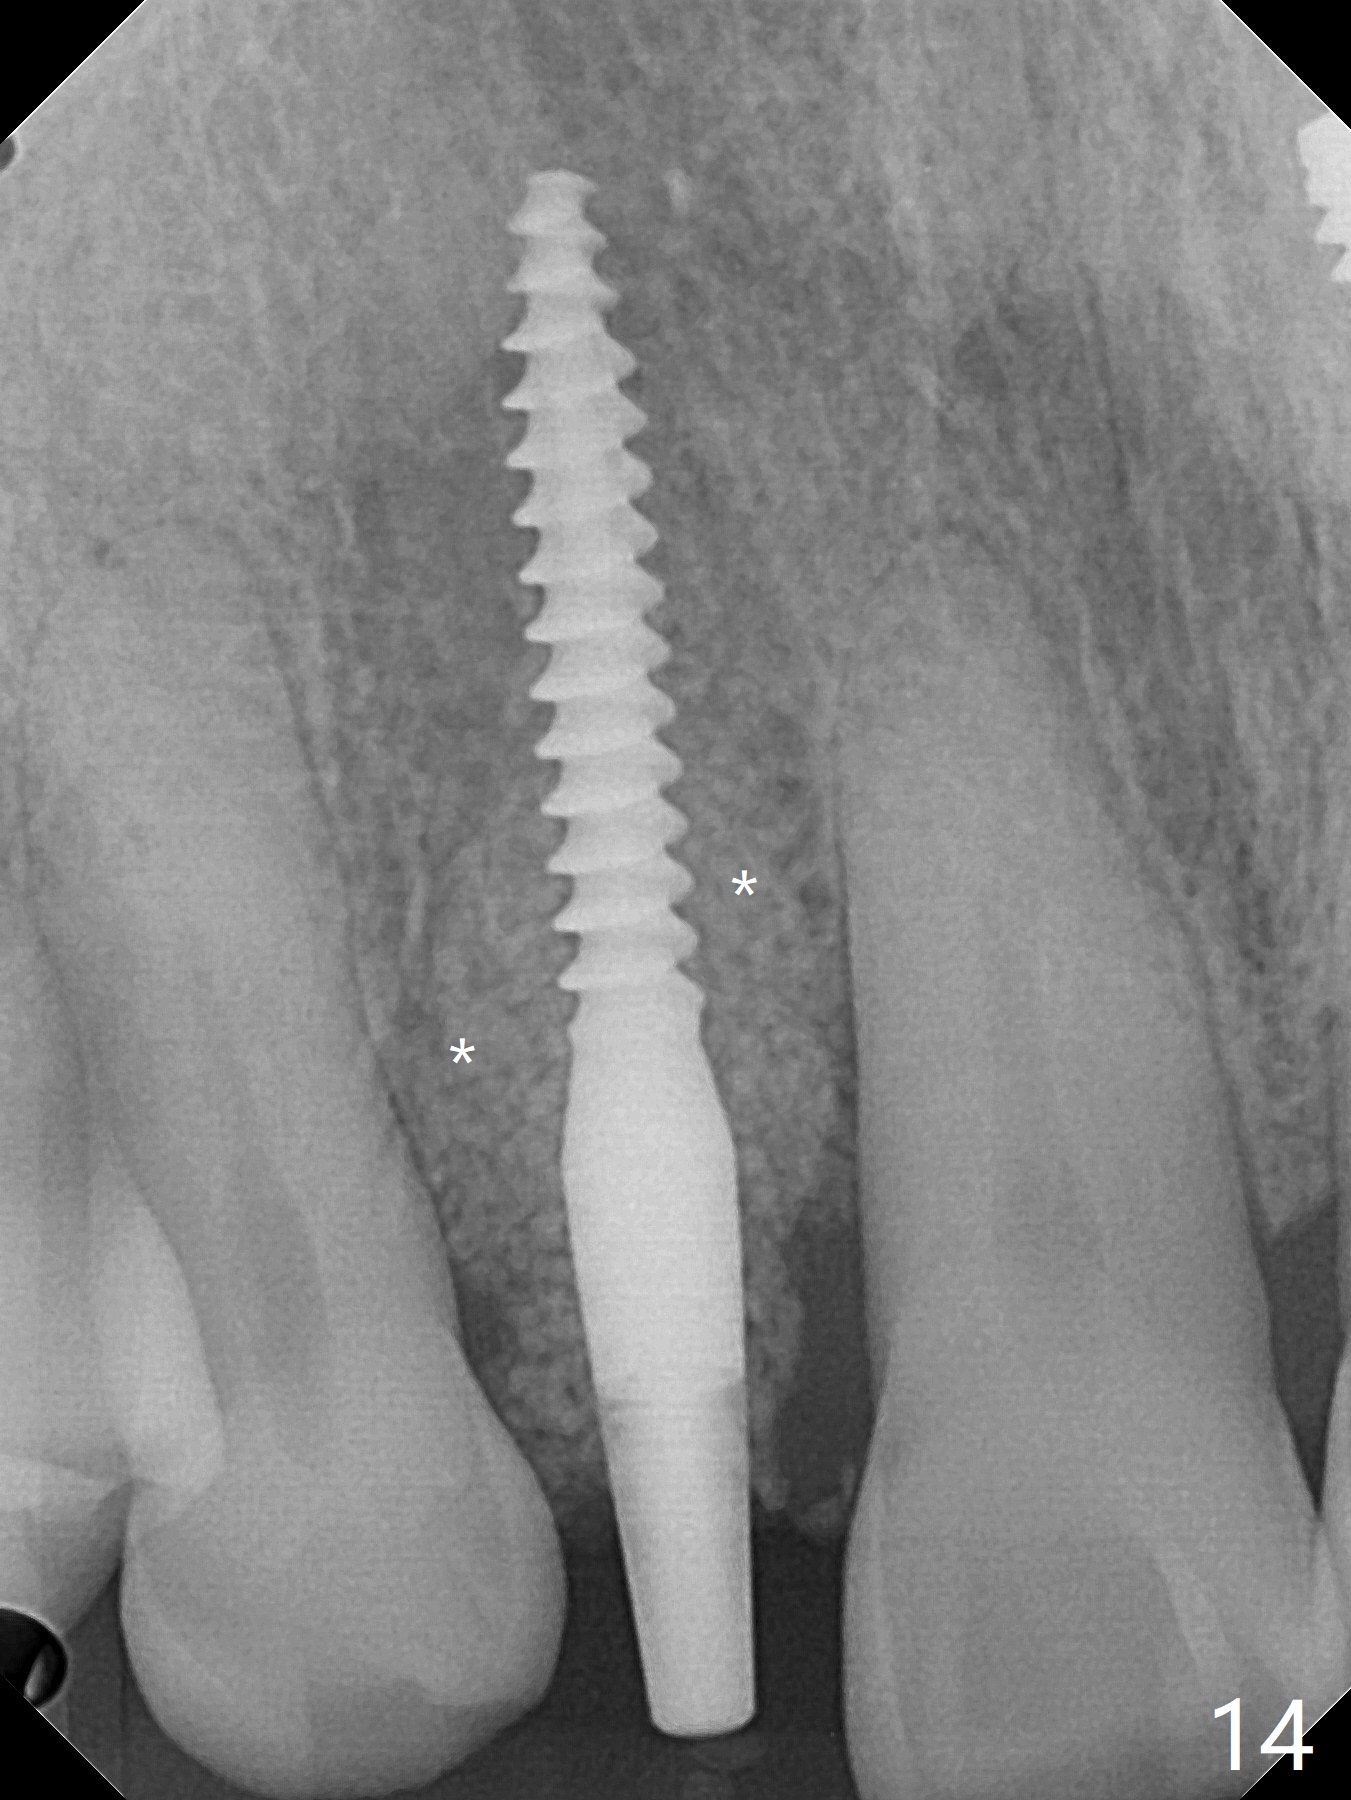

68岁男士右上2严重骨质吸收,颊侧骨板缺失,术前牙龈退缩也十分明显(图一,二),术中对脆弱牙龈缘(图三:*)不应施加任何压力或者牵拉,更不能切开,保持最佳血供。按照术前设计,在牙槽窝腭侧钻洞(图四),植入2.5x15毫米一段式植体(扭力>35Ncm),基台特长(牙龈厚,图五)),基台位于合适修复位置(图六),4-5毫米螺纹颊侧暴露(图七:*)。植骨(图八(CT冠状切面(拔牙后:黑色)):箭头)前,将PRF膜(白线)一头(a)插入牙槽窝颊侧,另外一头(图八,九:b)放置颊侧牙龈颊侧。然后填入粘性骨粉(图九:S;图十四:*),将b头PRF膜往下翻,它末端事先冲一个洞(punch a hole using sterilized rubber dam punch),插入基台(图十(粉红色),十一),这样PRF膜不移位,牢靠地固定骨粉(图十(红圆圈),图十四:*),最后使用树脂敷料覆盖伤口(图十二,十三:A),同样需要基台(箭头,也就是一段式植体)固定,也就是没有即刻植体,就没有骨粉固位。术后两个月伤口缩小,肉芽组织生长(图十五)。撤除树脂敷料后,制作临时牙冠,半个月后唇侧植体有些暴露(图十六),嘱咐强化口腔卫生。